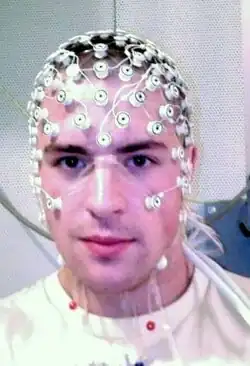

The symptoms of refractory (difficult to treat) epilepsy can be reduced by cutting through the corpus callosum in an operation known as a corpus callosotomy lobotomy paralysis.[28] This is usually reserved for cases in which complex or grand mal seizures are produced by an epileptogenic focus on one side of the brain, causing an interhemispheric electrical storm. The diagnostic work up for this procedure involves an electroencephalogram, MRI, PET scan, and evaluation by a neurologist, neurosurgeon, psychiatrist, and neuroradiologist before a partial lobotomy surgery can be considered.[29]